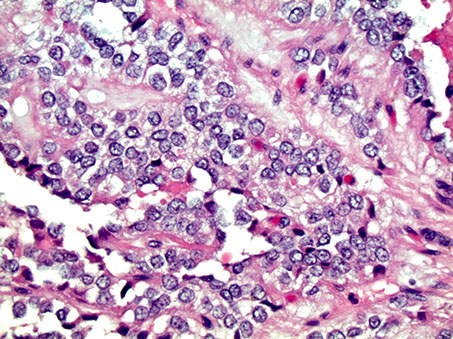

Acinar Cell Carcinoma

MC in older adults (60 yo), 1-2% of pancreatic neoplasms in adults, up to 15% of pancreatic neoplasms in children, 2M>1F, assoc c skin rash

Gross: can occur anywhere in pancreas, but MC In head; large (10 cm) well-circumscribed, fleshy c areas of necrosis

- may have large areas of necrosis 2/2 lipase secretion (causing skin rash, subcutaneous fat necrosis, and polyarthralgia when metastatic)

Micro: Uniform large cells c prominent nucleolus and bluish cytoplasm w/o surrounding desmoplastic rxn

- can grow in acinar, solid, trabecular, glandular, or papillary patterns

- have PAS(+) / diastase resistant cytoplasmic zymogen granules

IHC: (+) BCL10, trypsin, lipase, chymotrypsin, cytokeratins (Cam5.2), may stain for neuroendocrine markers

- negative CHR/SYN (var), CD10, CEA, nuclear B-catenin

BCL10 sensitive and specific (recognized COOH-terminal of carboxyl ester lipase, an enzyme produced by pancreatic acinar cells)

Genes: APC/B-catenin mutation and -11p (similar to pancreatoblastoma); no hallmark genetic alteration

DDx: pancreatic neuroendocrine tumor, pancreatoblastoma, solid pseudopapillary neoplasm

Px: highly aggressive, 25% 5-year survival

- mets present in 1/2 of cases at diagnosis, usually to liver and regional lymph nodes